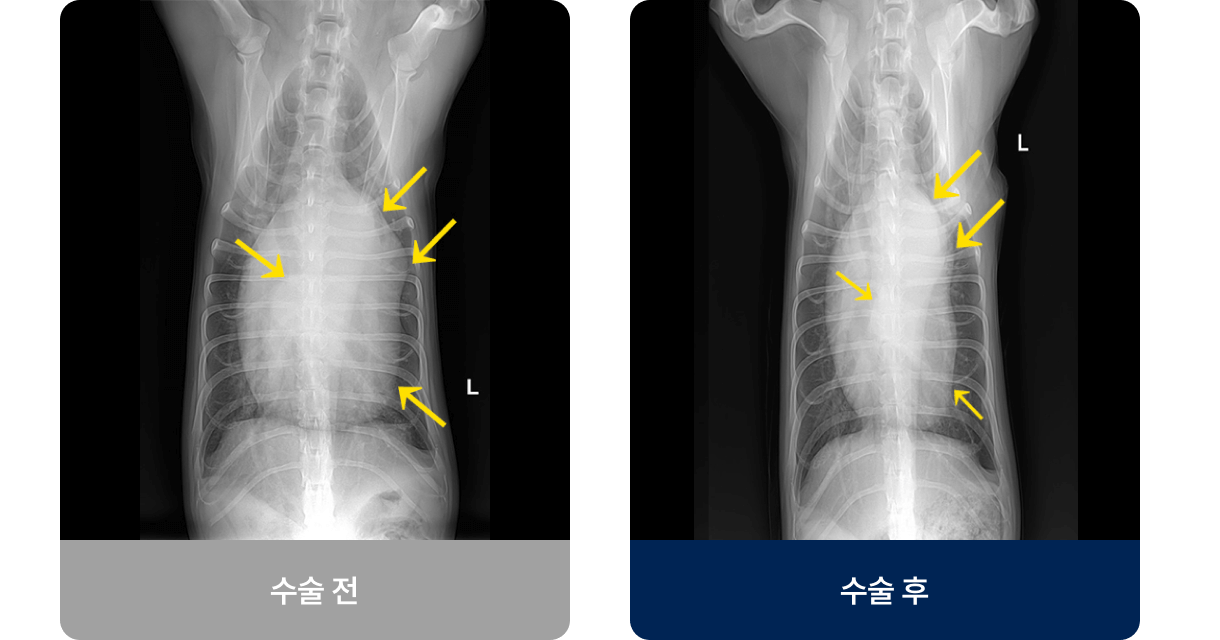

횡격막(가슴과 배를 구분하는 근육)에 구멍이 생겨, 간·위·장기 같은 복부 장기가 흉강 안으로 들어간 상태로, 이는 폐를 압박하고 폐가 완전히 팽창하지 못하게 하여 호흡 곤란을 유발합니다. 주로 교통사고나 낙상 등의 외부 충격으로 발생하며 호흡곤란, 구토, 식욕 저하 증상을 보입니다.